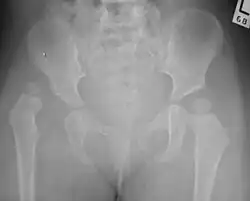

| Congenital dislocation of the left hip in an elderly person. Closed arrow marks the acetabulum, open arrow the femoral head. | |